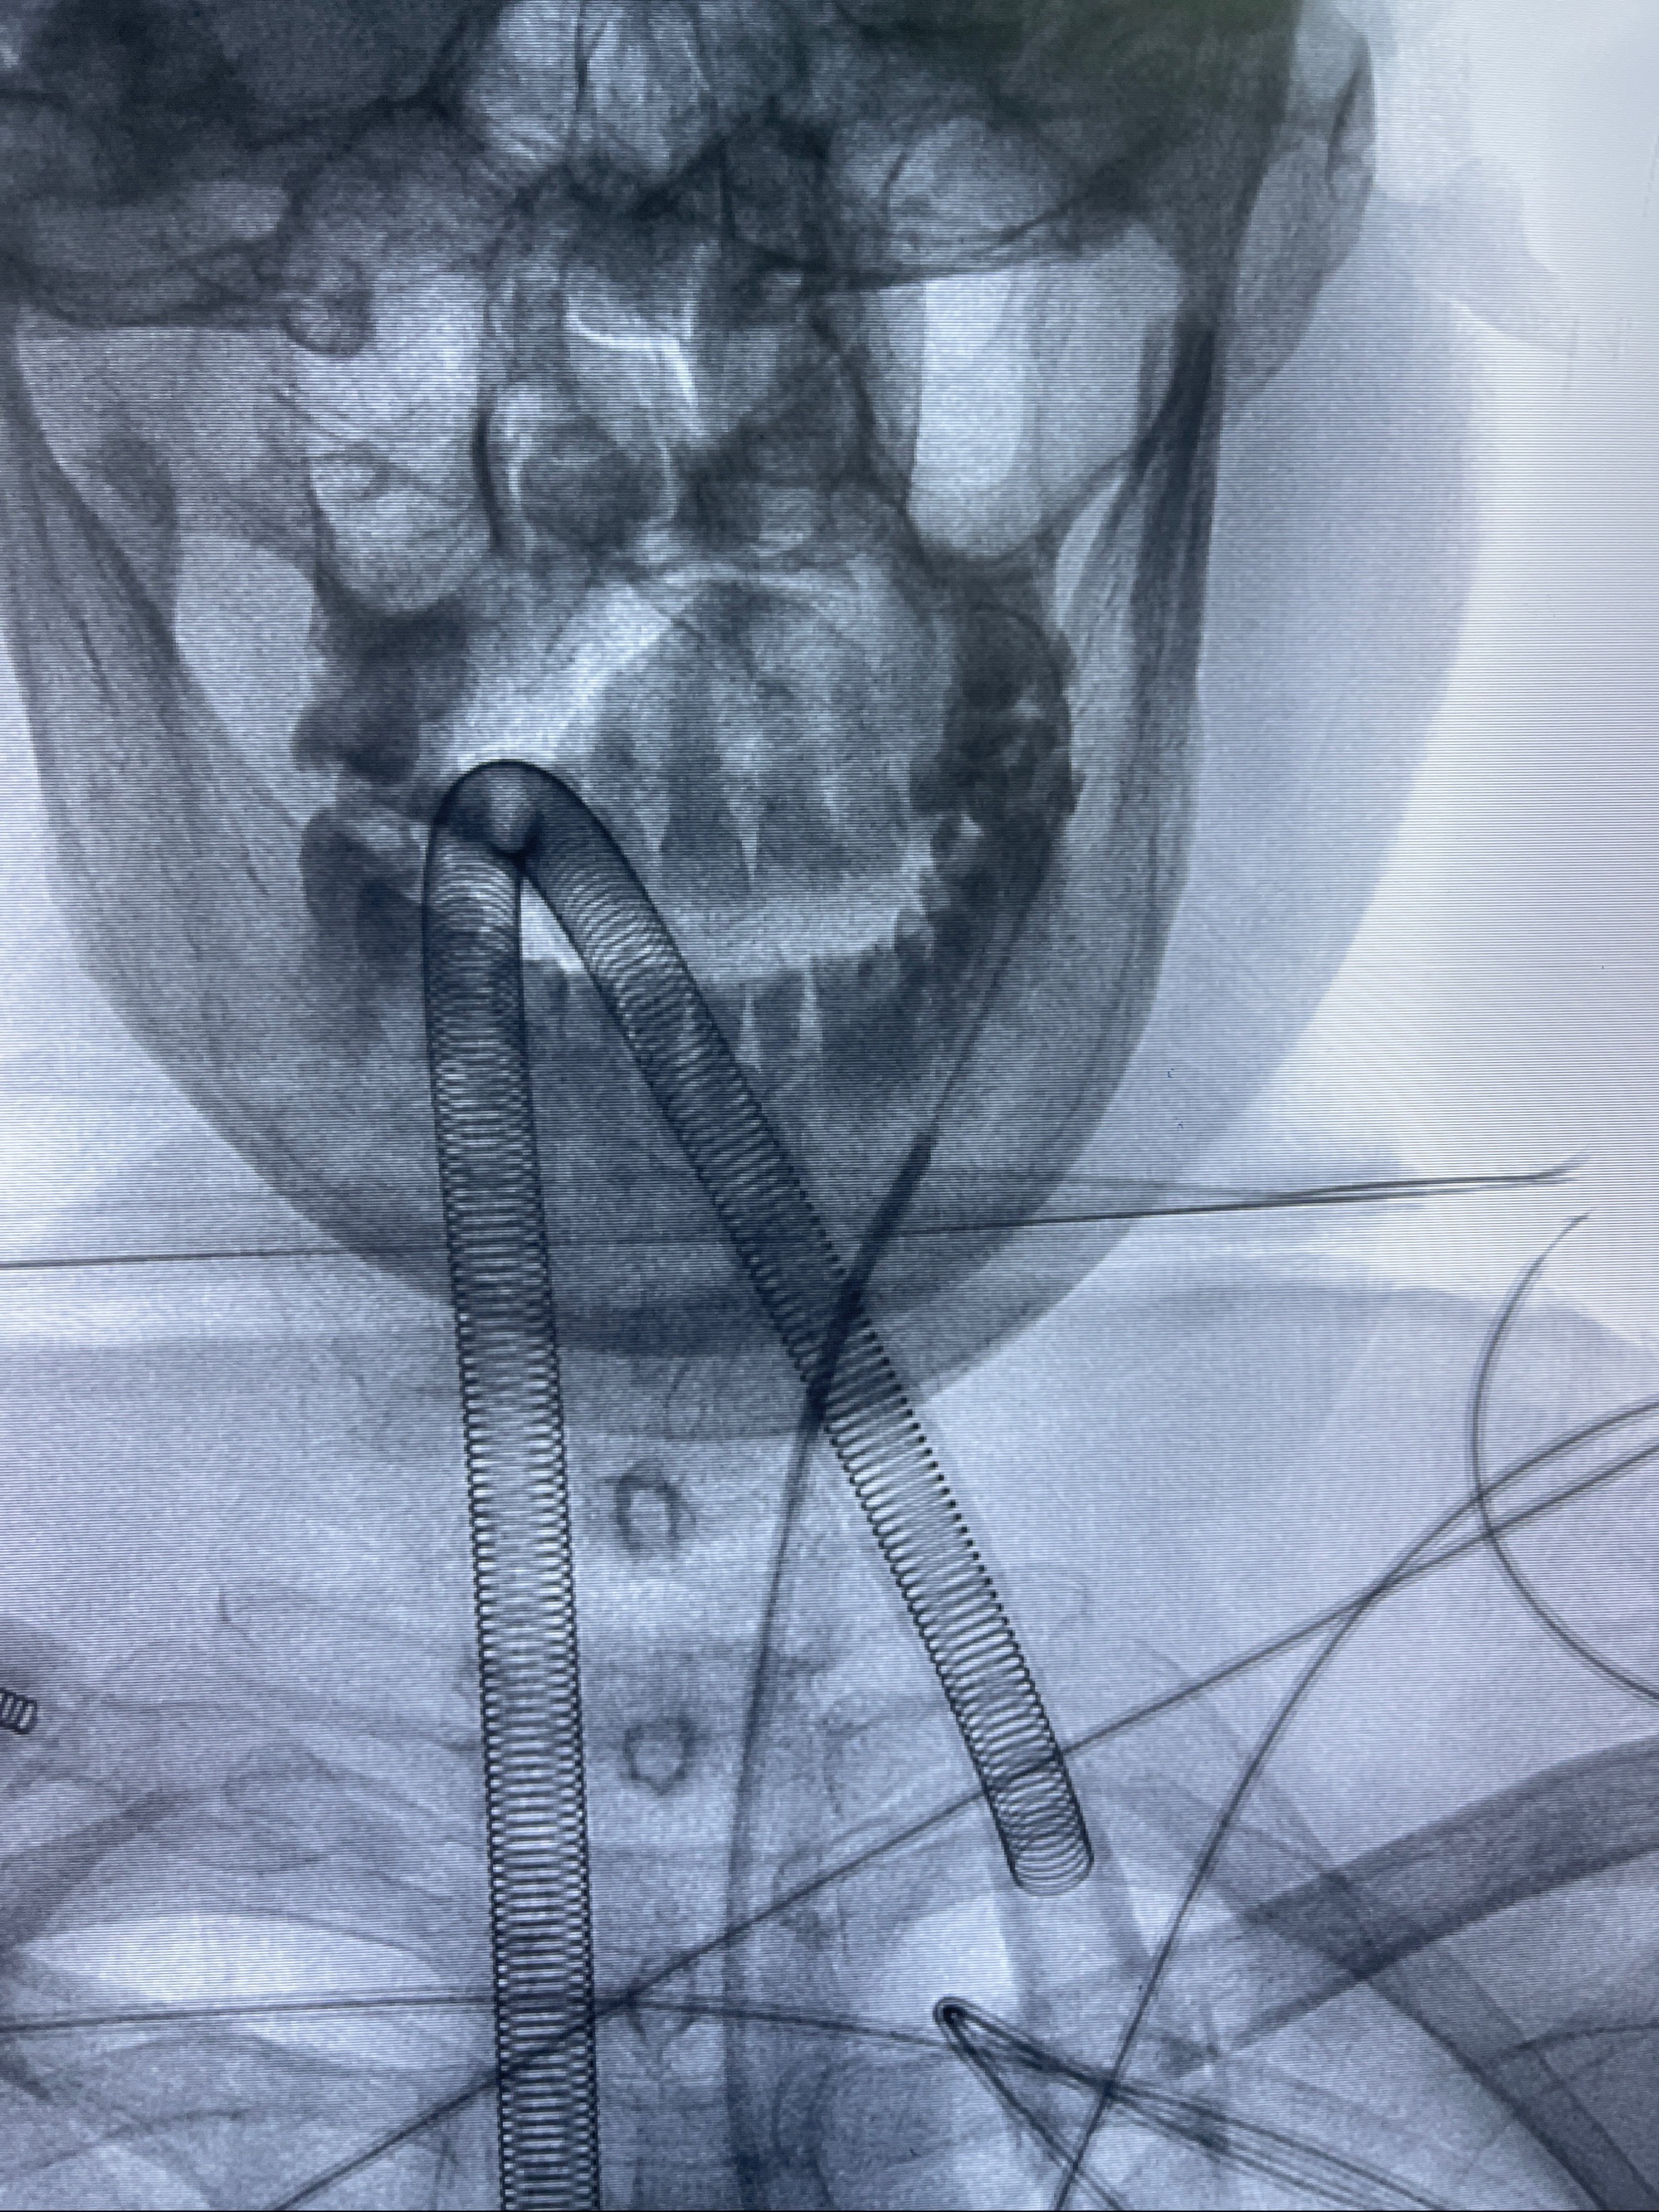

- 普微森088 90cm导引导管

- 125cmMPA

- 0.035泥鳅导丝

- TB支架导管